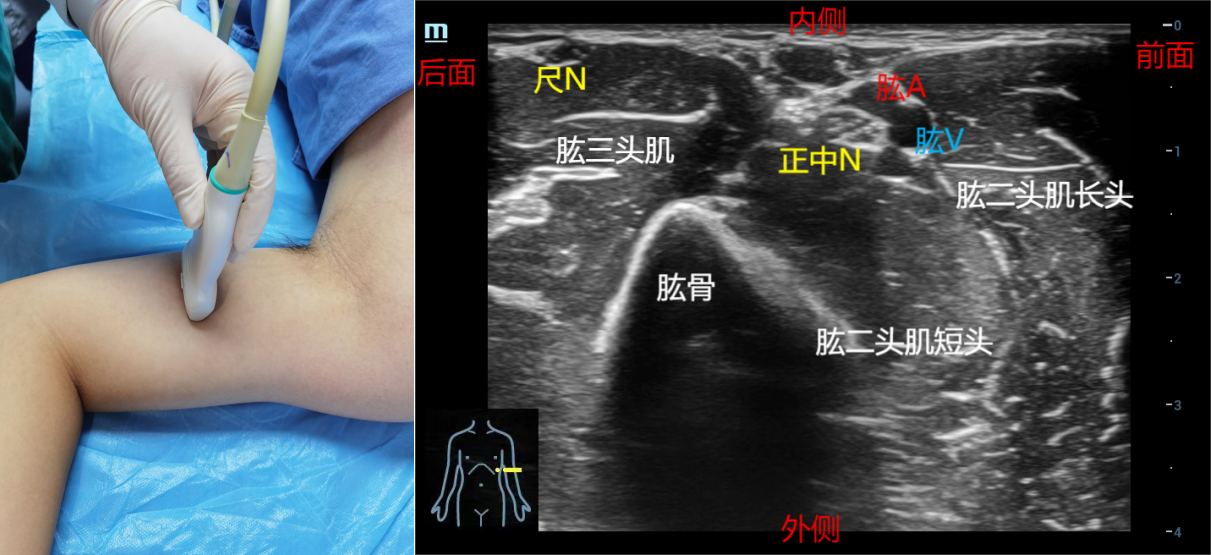

解剖关键点:上臂中段、肱动脉、肱骨中段。

①上臂中段入路。体位:平卧位,上臂外展。寻找正中神经的关键是找到肱动脉,然后顺肱动脉上下平移探头,寻找正中神经。探头放置在上臂中段,肱二头肌肌腹的内侧,正中神经在上臂一般走行在肱二头肌内。在上臂上段和中段正中神经在肱动脉的外侧或前侧。在中段以下,正中神经在肱动脉的内侧,并且在下段可观察到尺神经越来越远离肱动脉。推荐平面内法,从探头前侧进针。亦可以平面外法。